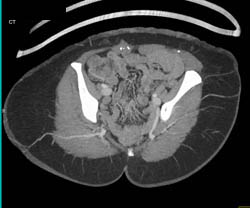

Nice CTA at Elbow